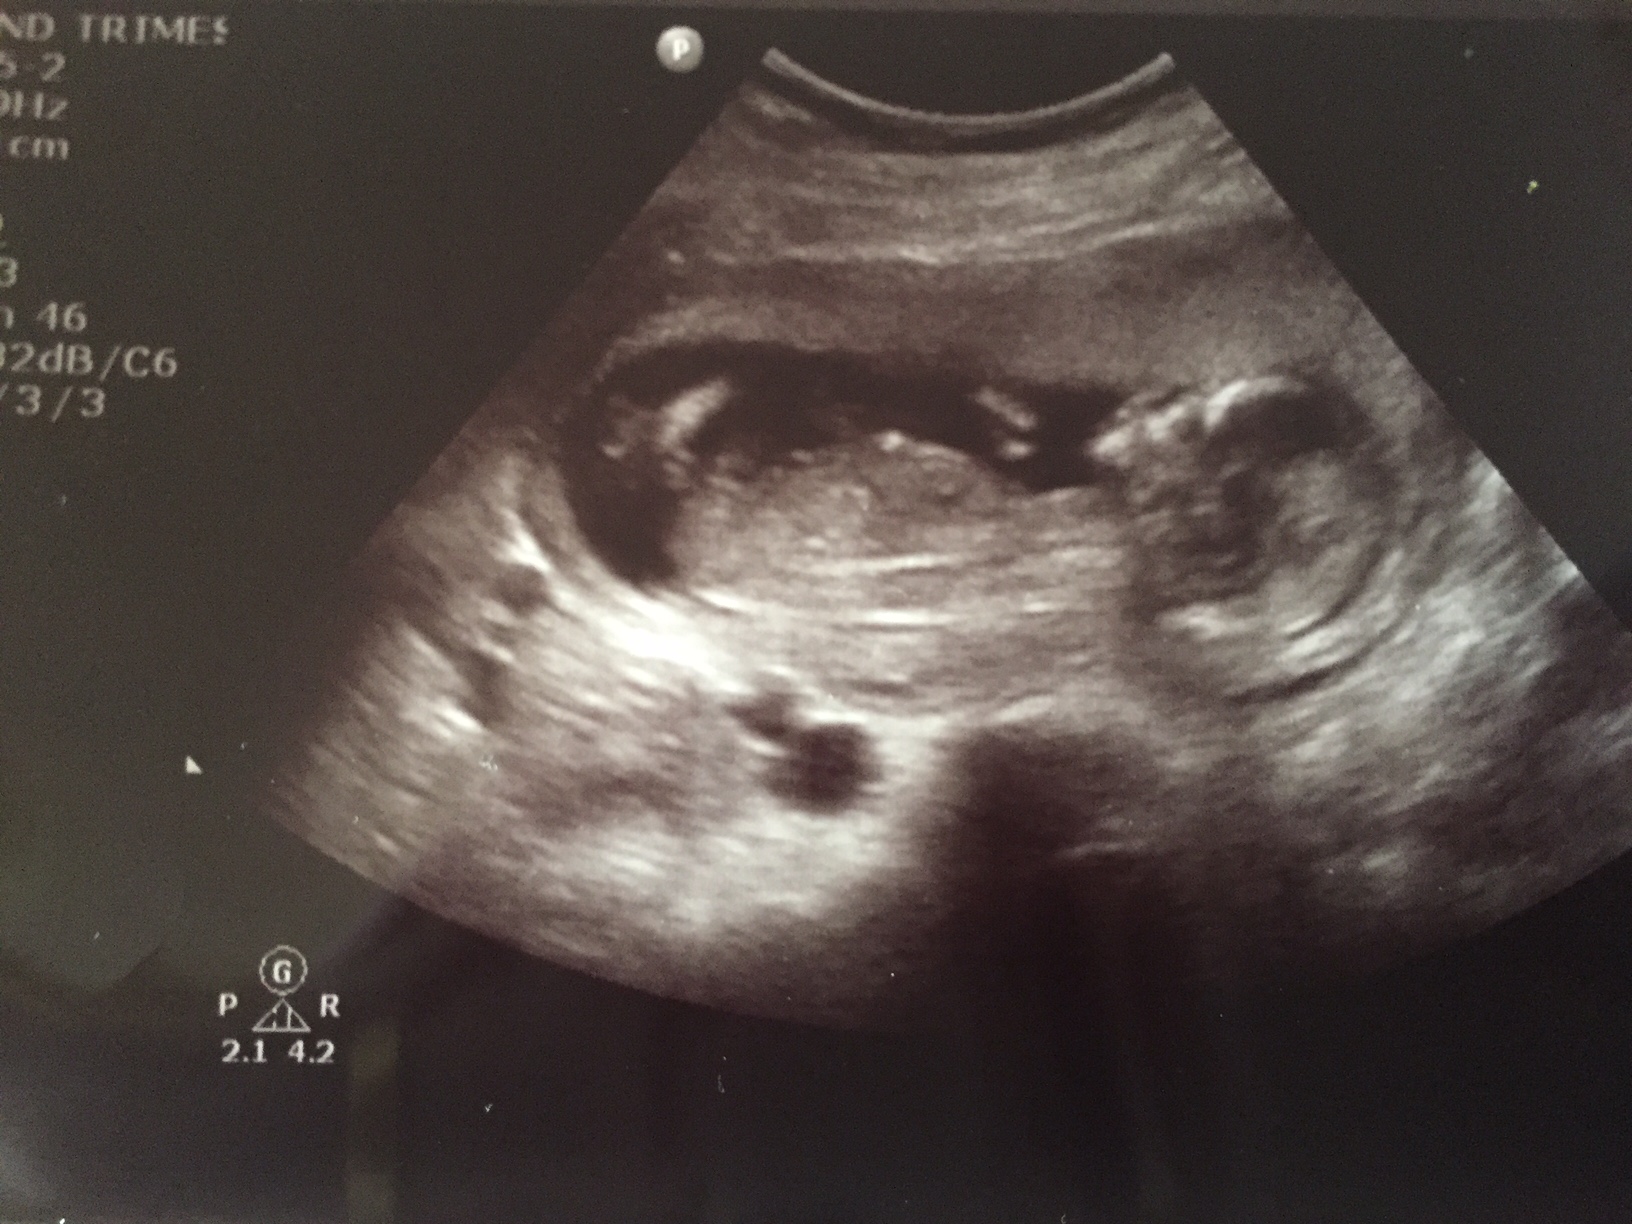

Hi! Just left an ultrasound, I'm 13w4d. The tech is my friend, she thinks boy but wants me to come back next week to confirm. I thought I'd post just to see what you guys think!

This is the shot from underneath that makes her think it's a boy. It's a screenshot from video so not great quality unfortunately.